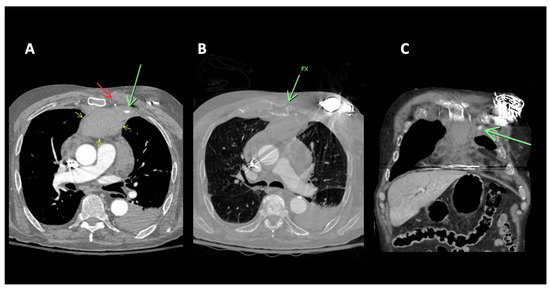

A 91-year-old-male with no significant past medical history presented following a motor vehicle accident. The patient, a rear seat restrained passenger, was involved in a front-end collision at 55 miles per hour. On admission, the patient complained of chest and abdominal pain. A seat belt shoulder strap injury was noted on the physical exam. In addition to a mediastinal hematoma, pulmonary contusion, sternal fracture, and multiple rib fractures, a CT scan of the chest showed active extravasation (Figure 1). Percutaneous intervention of the left internal mammary artery demonstrated a bilobed pseudoaneurysm arising from a LIMA side branch. Coil embolization was performed with the placement of detachable coils above, below, and across the origin of the side branch, the source of bleeding. Control percutaneous intervention after coil placement showed the cessation of extravasation and no further visualization of the pseudoaneurysm (Figure 2).

Figure 1. 91M MVA restrained rear seat passenger. (A) CT of the chest with contrast. Focal contrast extravasation consistent with active bleeding site left parasternal anterior mediastinum (green arrow). Left internal mammary artery (red arrow). Anterior mediastinal hematoma (yellow arrows). (B) CT of the chest, bone windows. Sternal fracture (green arrow). (C) CT of the chest with contrast coronal reconstruction. Focal contrast extravasation consistent with active bleeding site left parasternal anterior mediastinum (green arrow).